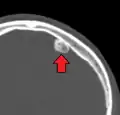

Osteoma of external auditory meatus